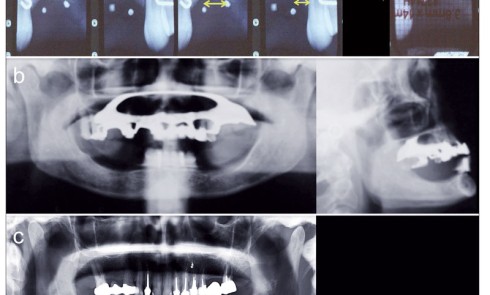

Imagerie

Article réservé à nos abonnés Imagerie dentomaxillaire par faisceau conique : principes, matériels, indications et dosimétrie

Article réservé à nos abonnés Imagerie en implantologie orale : étude pré-implantaire et planification

L’imagerie en implantologie orale est un élément essentiel de la démarche diagnostique, de la sélection des patients et de la...

Article réservé à nos abonnés Applications de l’imagerie en chirurgie orale : modalités et indications

Complémentaire et indissociable de l’examen clinique, l’imagerie est essentielle pour l’évaluation diagnostique et la prise en charge thérapeutique en chirurgie...

Article réservé à nos abonnés Examens radiographiques dentomaxillaires : principes, matériels et indications

L’imagerie médicale constitue une évaluation anatomique non invasive des éléments squelettiques et dentaires du massif maxillo-facial. Il s’agit également d’un...

Article réservé à nos abonnés Evolution de l’imagerie en parodontologie

Les maladies parodontales se traduisent par une altération des tissus parodontaux (gencive, ligament alvéolodentaire, cément et os alvéolaire). Leur prise...